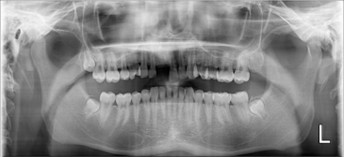

20代 男性

治療前

(薬・注射・レントゲン・CT・データ分析・骨造成・サージカルステント・血液検査・仮歯) - 年齢/性別

- 20代/男性

- 患者の具体的な症状

- 1年前に左上12 右上1の根の治療をし、その後放置していたら、左上2が破折した。

左上2インプラント補綴 左上1右上1オールセラミック装着。

歯根破折と虫歯による痛み、審美障害を主訴として来院。 - 検査方法

- コーンビームCT、レントゲン撮影

- 診断結果

- 左上2 歯根破折

- 治療詳細

- 左上抜歯後、インプラント埋入1本

骨造成あり 局所麻酔

インプラント治療後、左上1右上1セラミック修復2本 - 通院回数

- 9回

- 治療期間

- 12か月